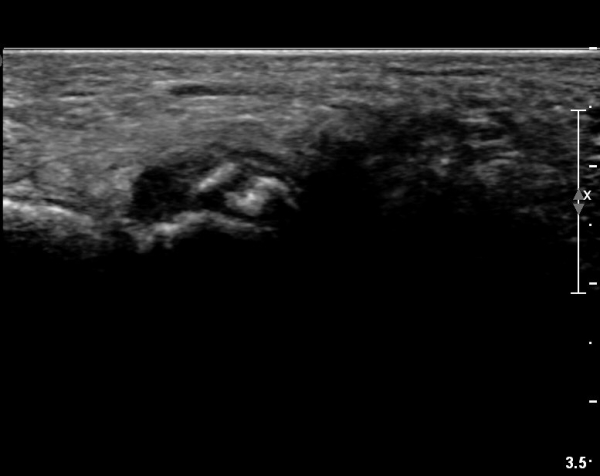

ŽÃËÀÚ¸¦ ¾à°£ ¾ÕÂÊ(¹ß ¿ÜÃø)À¸·Î À̵¿ÇÏ´Ï Á¾ÀÚ»À¿¡ ºÙ´Â Àåºñ°ñ°ÇÀÌ °üÂûµÇ°í °Ç ÁÖÀ§ ºÎÁ¾ÀÌ °üÂûµÊ(»çÁø 2, 3).

ŽÃËÀÚ¸¦ Á» ´õ ±ÙÀ§ºÎ·Î À̵¿ÇÏ¿© Àåºñ°ñ°ÇÀÇ Á¾´Ü¸é ±ÙÀ§ºÎ ¿µ»óÀ» È®ÀÓÇÔ(»çÁø 4)